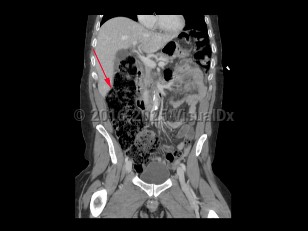

Patients present with severe abdominal distension and inability to pass stool or flatus. Abdominal pain due to LBO is typically less severe and more gradual in onset compared to SBO. However, patients with LBO typically have more severe distension compared to SBO, as well as nausea and vomiting.

Patients presenting secondary to colorectal malignancy often have a history of alternating diarrhea and constipation over the preceding weeks to months and may have had bleeding per rectum. A change in stool caliber and/or weight loss may be present and suggest malignancy is the cause of the LBO. Left lower quadrant (LLQ) pain can be suggestive of diverticular disease. Sigmoid volvulus is more common in older patients, those on a high-fiber diet, those with a history of chronic constipation, and long-term care facility residents. Cecal volvulus differs in that it occurs most commonly in patients between the ages of 30 and 60 years and in those with a pelvic mass, prior abdominal surgery, and in the third trimester of pregnancy.

Obstruction leads to increased colonic dilation, eventually leading to necrosis and perforation of the bowel. Patients with bowel ischemia or perforation usually have more severe presentations, often with signs of peritonitis, sepsis, and hemodynamic instability.